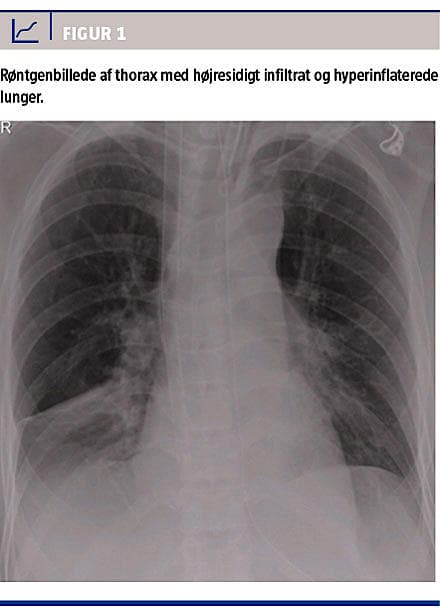

niveauet. En røntgenundersøgelse af thorax viste hyperinflaterede lunger og et højresidigt infiltrat (Figur 1). Man påbegyndte empirisk antibiotisk behandling med cefuroxim pga. leukocytose og et C-reaktivt proteinniveau på 67 mg/l. Efter 12 timer blev patienten atter svært bronkospastisk og hypotensiv. Da ventilation med et toptryk på 40 cm H2O og en frekvens på 10 kun gav små tidalvolumina og hypotension, forsøgte man håndventilation med sevofluran og adrenalininfusion (0,2 mikrogram/kg/min), men PaCO2-niveauet steg til 22 kPa med en pH på 6,90.